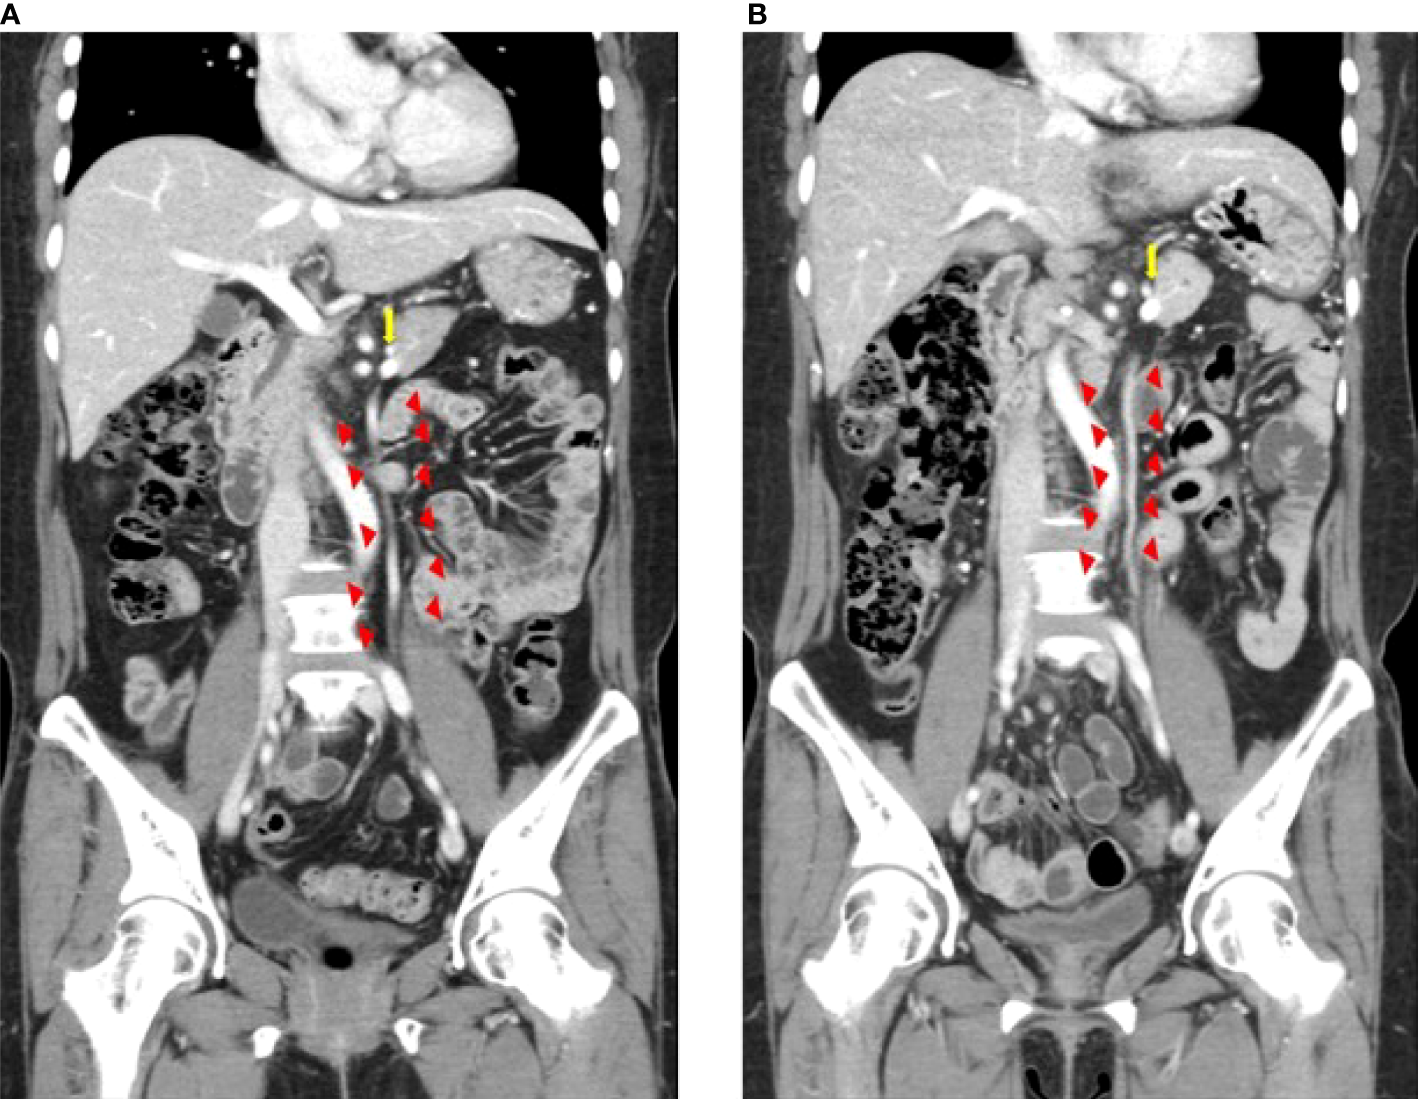

The technical success rate was measured among patients who underwent IMV preservation. The technical success of IMV preservation was determined by assessing the post-operative patency of IMV on CT. A board-certified abdominal radiologist (J.H.P, 11 years of clinical experience) retrospectively reviewed the pre- and post-operative CT images and rated the patency of the IMV using a 3-point scale, where grade 1 indicated no change in patency, grade 2 indicated that the patency had decreased by 30% or more, and grade 3 indicated that the IMV was not visualized (Figure 3) (26). The radiologist was aware of patient eligibility criteria and might have determined the surgical technique through the image review, but was blinded to the purpose of this study and other clinical information.

Figure 3

Inferior mesenteric vein preservation confirmed on computed tomography images before (A) and after surgery (B) Triangles indicate the inferior mesenteric vein. The arrow indicates the splenic vein.